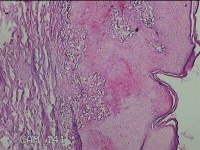

右侧腰臀部包块

性别

女

年龄

44岁

临床诊断

臀部良性肿瘤

一般病史

发现右侧腰臀部包块1个月余。

标本名称

大体所见

灰白粉红色包块0.8x0.3x0.2cm一个,表面光滑。

图1

良性病变。